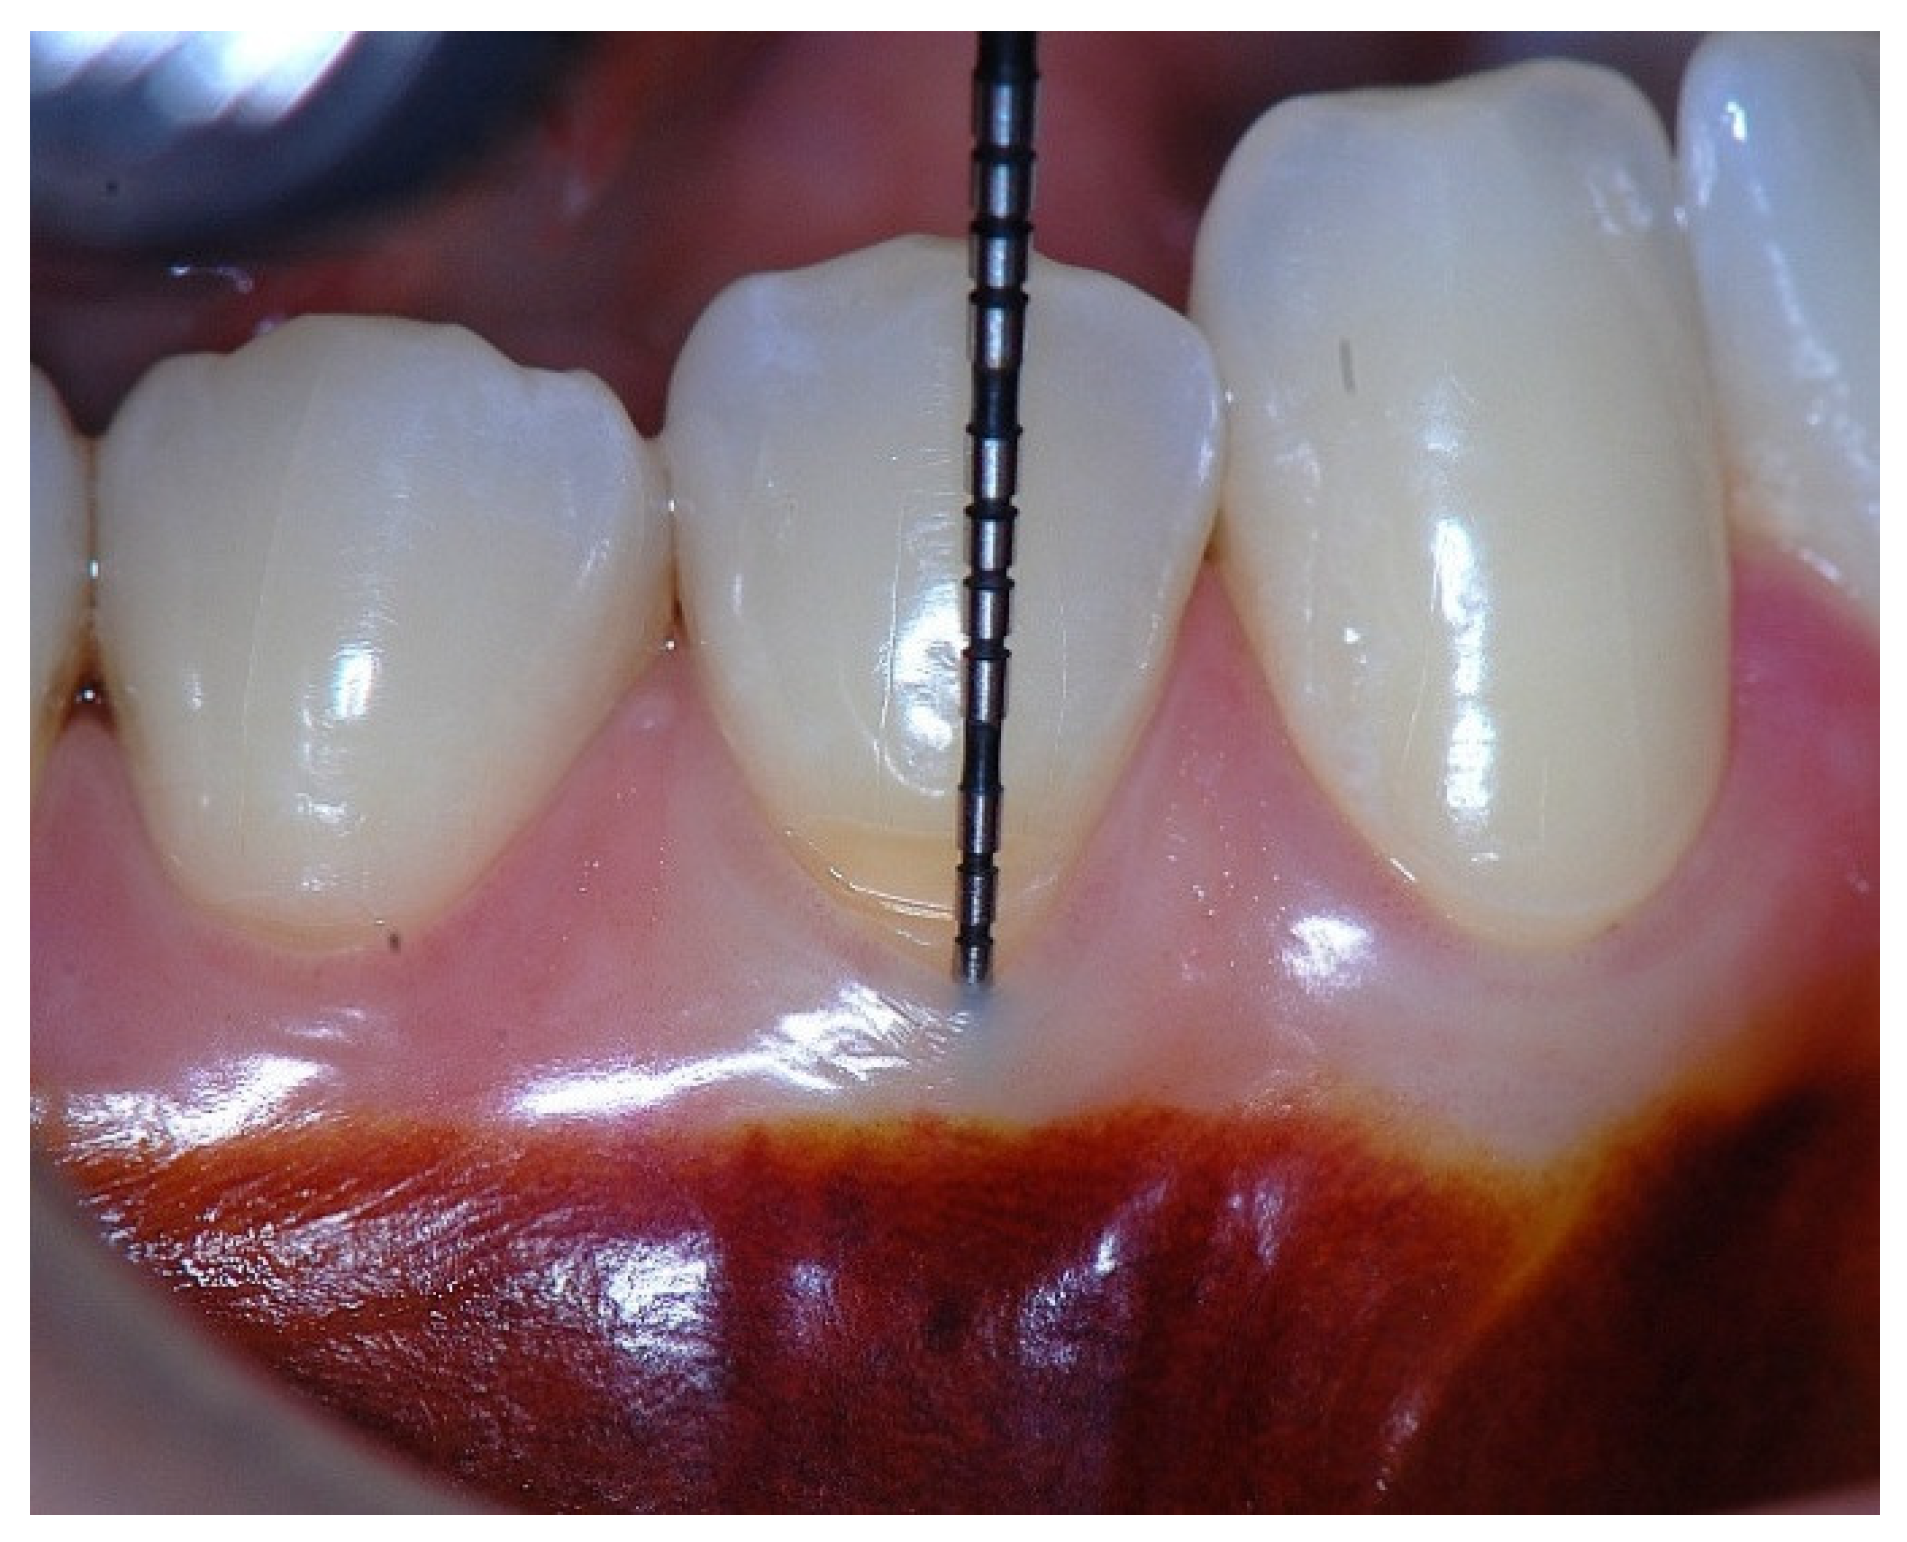

Figure 4. Clinical image of tooth #29 showing an insufficient width of attached gingiva.

In a clinical scenario with 2 mm of keratinized tissue (KT) and a sulcus depth of 1 mm, a stable, firm, and resistant connective attachment is not present [1]. This occurs because most of the connective tissue fibers inserting onto the root surface are associated with non-keratinized, mobile mucosal tissues (Figure 1), which are elastic in nature and therefore unable to stabilize the gingival margin (Figure 4 and Figure 5). Conversely, when these fibers are embedded within keratinized tissue, they are firmly attached to the tooth and bone and are comparatively immobile, thereby contributing to gingival margin stability (Figure 2, Figure 3, and Figure 6).

Figure 1. Probing depth of 1mm and 1mm of the epithelial attachment.